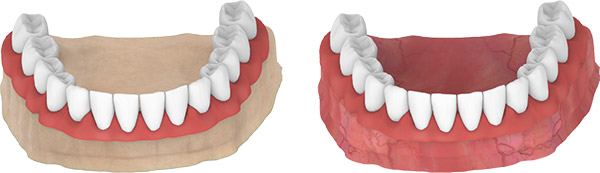

LABORATORY PROCESSES

- Mount the analogs carefully on impression pick up pieces.

- Prepare the impression for transfer.

- Cast high-quality material for the master model.

- The model is restored in the dental laboratory.

- Place the abutment on top.

MULTI UNIT

LOCATOR ABUTMENT

CLOSED TRAY IMPRESSION TECHNIQUE

- Use the straight and/or 17-degree Multi Base Locator Abutment in the anterior region.

- Use the 30-degree Multi Base Locator Abutment in the posterior region.

- Mount the plastic pick up transfers used for impression on 17-30 degree Multi Base Locator Abutments.

- Take the impression.

Note: The recommended insertion torque when screwing the abutment is 25 Ncm.

LABORATORY PROCESSES

- Mount the analogs carefully on impression pick up pieces.

- Prepare the impression for transfer.

- Cast high quality plaster for the master model.

- The model is restored in the dental laboratory.

- Place the abutment on top.